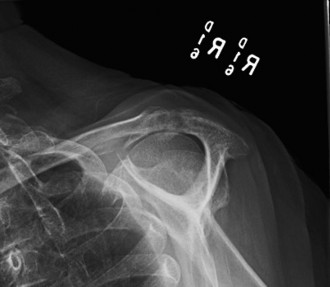

Treat a patient with infected total shoulder arthroplasty? CASE 21 A 70-year-old, right-hand-dominant female presents to clinic complaining of 4 years of gradually worsening chronic right shoulder pain and stiffness. She says the pain is worse at night and with any range of motion, denies a history of trauma, pain in other extremities, or numbness or tingling of the right upper extremity. She notes that her mother suffered from rheumatoid arthritis that affected her shoulder. Physical examination reveals decreased muscle bulk over the right supra- and infraspinatus fossae compared to the contralateral side, limited active and passive ROM, marked weakness with external rotation, and 4+/5 strength with shoulder abduction. X-rays of the right shoulder are shown in Figures 2–58 and 2–59.

Figure 2–58

Figure 2–59

The correct answer is (C). Rotator cuff tear arthropathy consists of a combination of rotator cuff insufficiency, glenohumeral joint degenerative changes, and superior humeral head migration. It is more common in women and also more often found on the dominant side. The patient’s clinical examination with weakened external

rotation and muscle atrophy signaling incompetent supra- and infraspinatus muscles point to rotator cuff insufficiency, and her plain films reveal narrowed glenohumeral joint space as well as superior migration of the humeral head. Choice D is incorrect because, while radiographs would show narrowing of the glenohumeral joint space, they would also likely show numerous osteophytes and posterior wear of the glenoid. Choice B is incorrect because, while adhesive capsulitis does present as decreased active and passive range of motion, the patient’s constellation of symptoms pointing towards rotator cuff insufficiency along with the radiographs make cuff tear arthropathy the more likely choice. Finally, Choice A is incorrect because even though she has a positive family history of rheumatoid arthritis, it is less likely to present only in a single joint. Also, rheumatoid arthritis on radiography appears more as an erosive process without the characteristic superior migration of the humeral head.

The correct answer is (A). Superior migration of the humeral head would be most indicative of chronic rotator cuff insufficiency associated with cuff tear arthropathy, as it is a direct result of the inability of the rotator cuff tendons to help maintain the humerus in its normal position. Acetabularization of the undersurface of the acromion is commonly associated with superior migration of the humeral head found in rotator cuff tear arthropathy, and can be assessed using the Hamada classification, which is based on measurements of the acromiohumeral interval on radiography (Table 2–8). Choices B and C are incorrect because, while narrowed glenohumeral joint space and subchondral sclerosis are associated with rotator cuff arthropathy on radiographs, they indicate degenerative joint changes rather than chronic rotator cuff insufficiency. Choice D is incorrect because it is not a specific sign of rotator cuff arthropathy.